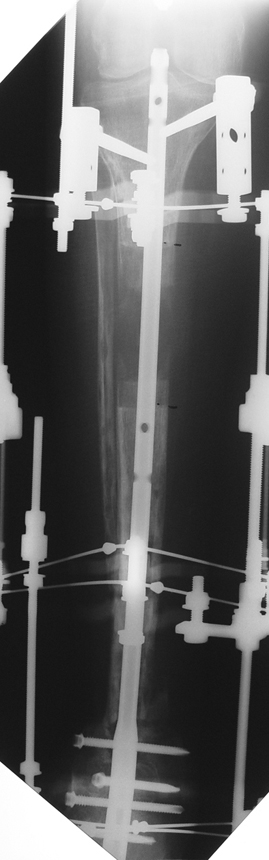

Recently, ilizarov techniques which is basis depend on distraction osteogenesis , bone segment transport or acute shortening after the resection at the site of pseudarthrosis combined with lengthening at another level of bone have been used. These treatment techniques may include some advantage for problems of infection, leg-length discrepancy, soft-tissue loss, and joint contracture.

Case 3